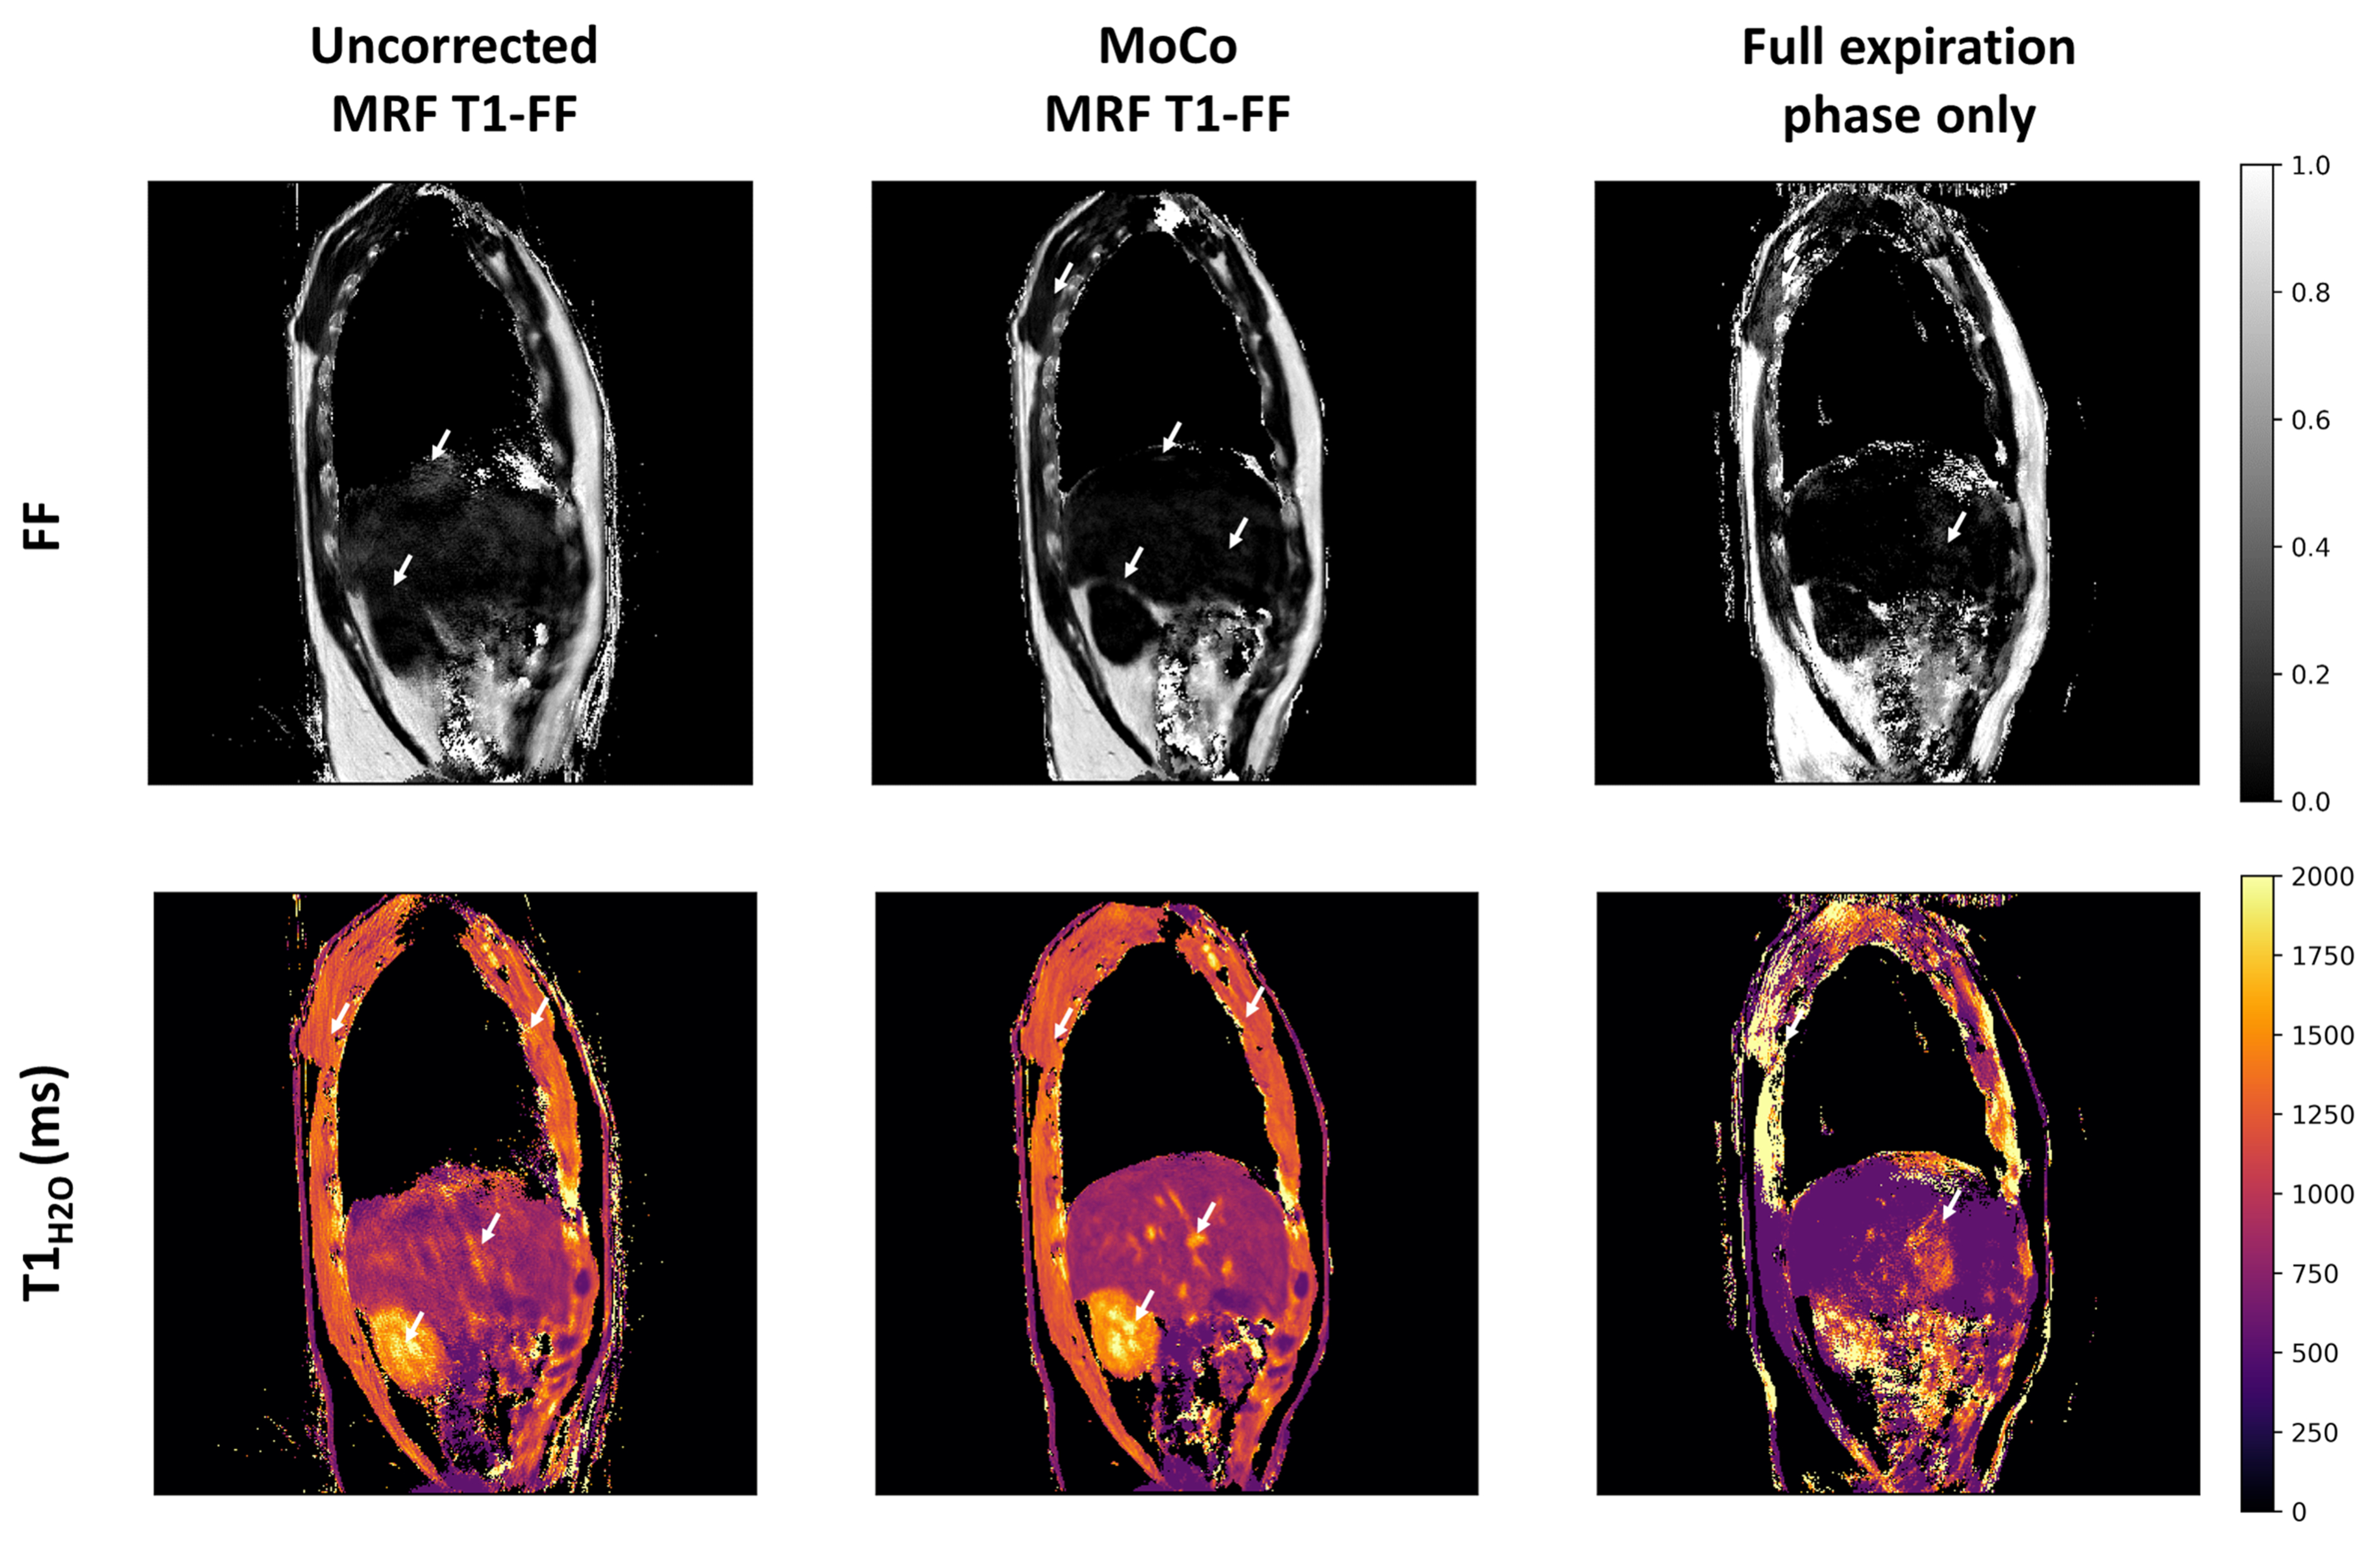

As a result of this motion correction, the MRF parametric maps exhibited significantly enhanced sharpness and reduced artefacts (Fig.6). Notably, on the T1H2O𝑇subscript1𝐻2𝑂T1_{H2O} maps, distinct anatomical features of the liver such as the dome and vessels become more discernible, while FF decreased and exhibited greater uniformity. Moreover, the kidney calyx was clearly delineated on the T1H2O𝑇subscript1𝐻2𝑂T1_{H2O} maps, and motion-induced blurring in the renal medulla vanished on the FF maps. Streaking artifacts in the pectoral, dorsal, and abdominal muscles were noticeably diminished. Reconstruction using only spokes from the full expiration phase showed severe undersampling artefacts and strong bias in FF and T1H2O𝑇subscript1𝐻2𝑂T1_{H2O} estimation. Furthermore, the diaphragm could be detected on several slices of the MoCo MRF T1-FF maps, indicated by a thin arch devoid of fat between the liver and the heart (Fig.7). This region corresponded to a slender muscle layer clearly outlined on the T1H2O𝑇subscript1𝐻2𝑂T1_{H2O} maps.

Refer to caption

Figure 6: Representative parametric FF and T1H2O𝑇subscript1𝐻2𝑂T1_{H2O} maps obtained at one slice level in a healthy volunteer derived from the uncorrected and motion-corrected (MoCo) MRF T1-FF reconstructions, and from the MRF T1-FF data acquired during the reference respiratory phase only (corresponding to the full-expiration phase). White arrows emphasize regions where motion blurring, parameter estimation bias and streaking artifacts are significantly mitigated with the motion correction method.